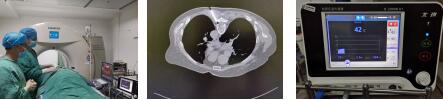

今年七月中旬,疼痛科收入住院,对患者进行“胸椎硬膜外连续自控镇痛”治疗。4天后,副主任医师王中胜带领白长叙医生对患者实施了目前临床上先进的彩超联合CT引导下胸5-7神经射频调节术(微创手术),这个技术对病变受累神经功能进行直接调节,从而能达到很快地明显改善患者的疼痛和各项临床症状,经过1个多周的治疗,患者疼痛明显缓解,满意出院。

郭阿姨就诊时:疼痛评分6分。

市中医院疼痛科治疗方案:

第一步:胸椎硬膜外连续自控镇痛+对症药物治疗

第二步:彩超联合CT引导下胸5-7神经射频调节

治疗结果:疼痛评分为1—2分,疼痛明显缓解,效果显著,由入院时的焦虑不安到出院时微笑满面,患者十分满意。